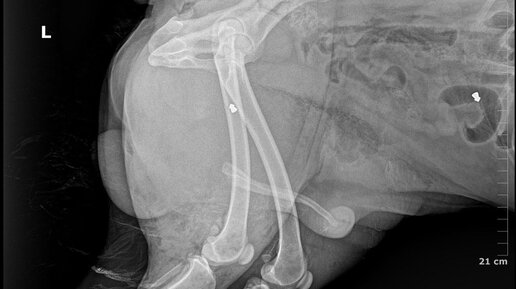

Как стало известно “Prime News”, 31 марта в Речице на АЗС номер 23 по Светлогорскому шоссе речичанами была обнаружена раненая собака. Неравнодушные горожане связались с волонтёрами социально-благотворительного учреждения “Дом с хвостом”. Пёс был доставлен в ветклинику города Гомеля, где скончался практически по приезду от полученных ран...